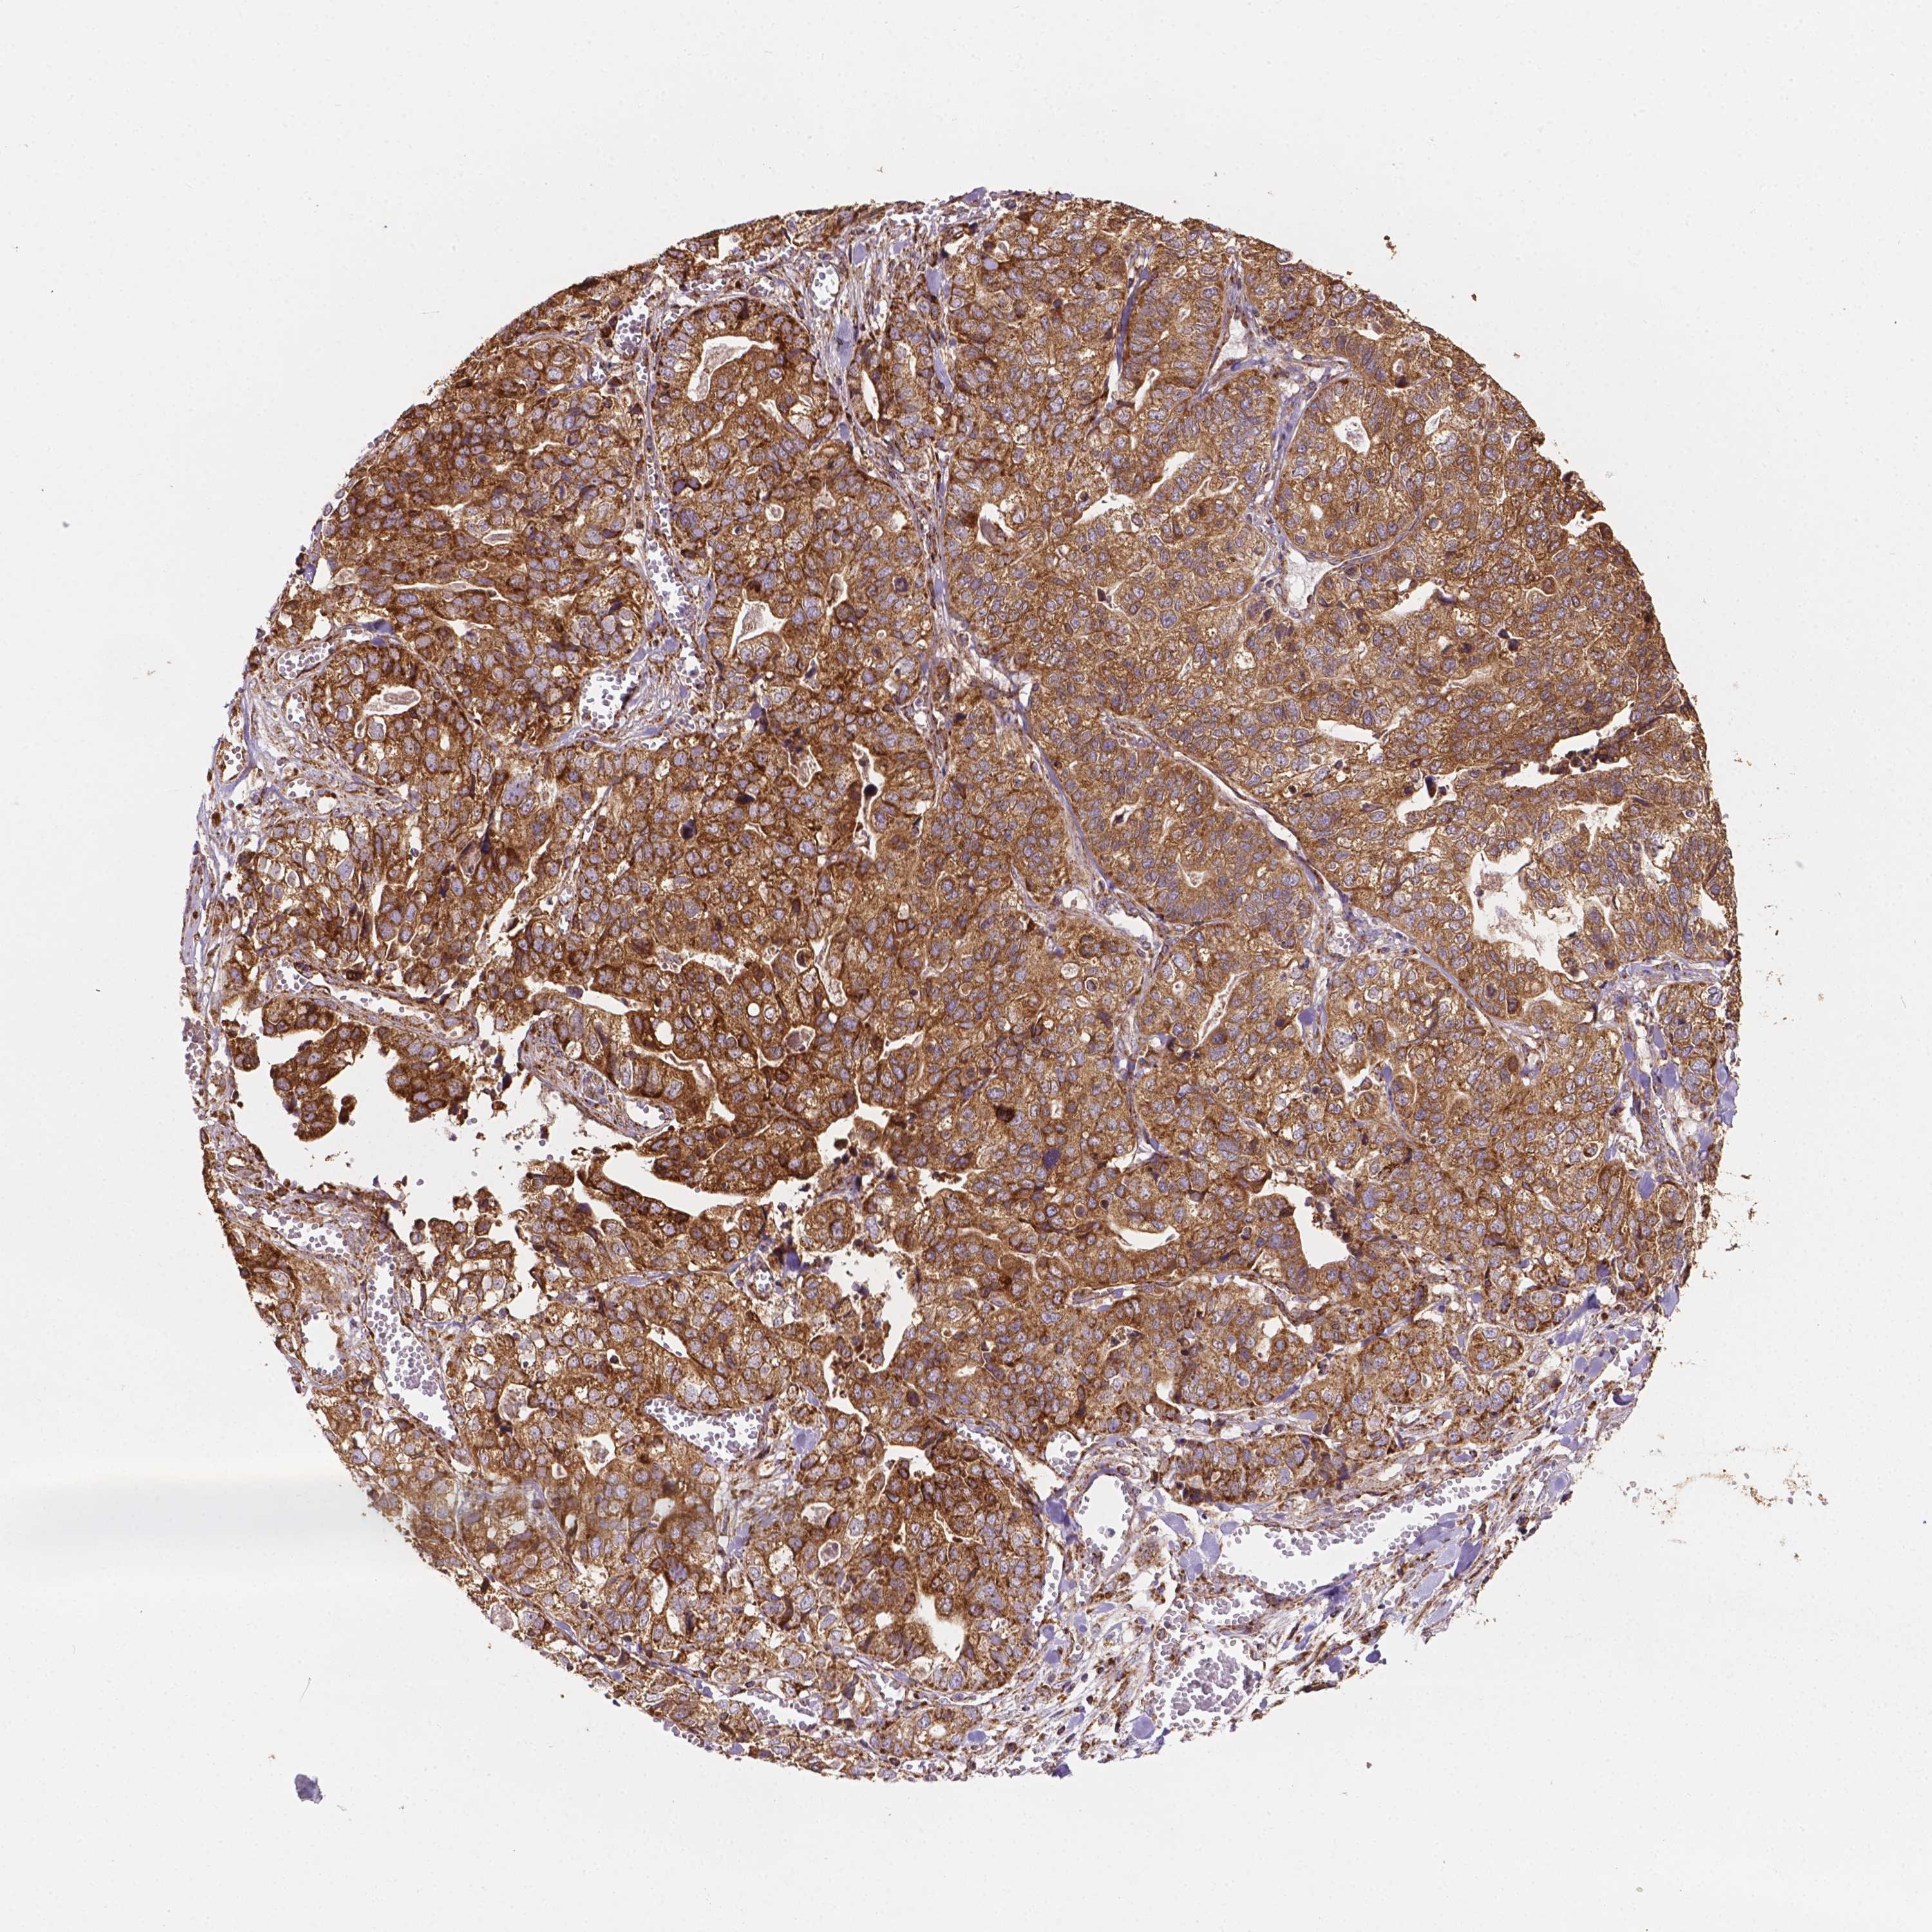

STOMACH CANCER - Protein expressioni

A mouse-over function shows sample information and annotation data. Click on an image to view it in a full screen mode. Samples can be filtered based on level of antibody staining by selecting one or several of the following categories: high, medium, low and not detected. The assay and annotation is described here.

Note that samples used for immunohistochemistry by the Human Protein Atlas do not correspond to samples in the TCGA dataset.

Antibody stainingi

Antibody staining in the annotated cell types in the current human tissue is reported as not detected, low, medium, or high, based on conventional immunohistochemistry profiling in selected tissues. This score is based on the combination of the staining intensity and fraction of stained cells.

Each image is clickable and will lead to virtual microscopy that enables deeper exploration of all samples and also displays staining intensity scores, fraction scores and subcellular localization as well as patient and tissue information for each sample.

Antibody HPA067682

Staining

High

Medium

Low

Not detected

Intensity

Strong

Moderate

Weak

Negative

Quantity

>75%

75%-25%

<25%

None

Location

Nuclear

Cytoplasmic/membranous

Cytoplasmic/membranous,nuclear

Adenocarcinoma, NOS